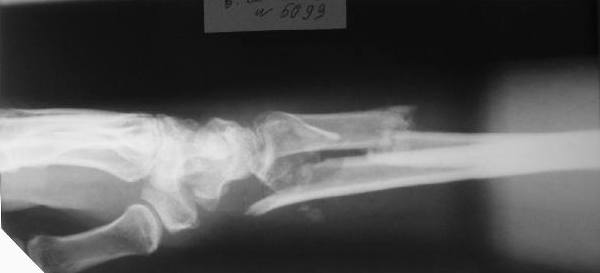

Больному 27 лет. Травма 2 месяца назад, проводилась закрытая репозиция. Контрольные снимки 3 недели назад (смотреть вложение).

Планируем провести открытую репозицию фиксацию пластинами.

Обдумываем, как провести репозицию? Предварительно провести дистракцию аппаратом внешней фиксации за нескольких дней до открытой репозиции или во время открытой репозиции?

Первоначальное впечатление: если край проксимального отломка лучевой кости не давит на срединный нерв и не нарушает скольжение сгибателей, то достаточно быстро пациент сможет вернуться к труду при продолжении консервативного лечения. Укорочение на 15 мм для неопорного (да и для опорного тоже) сегмента некритично. Имеющиеся осевые смещения вполне компенсируются запасом диапазона фукции суставов. Если край проксимального отломка мешает -- можно резецировать его, не разрушая сфорировавшегося к сегодняшнему дню сращения.

В аналогичном случае мы бы лечили больного с использованием чрескостного остеосинтеза, трансформируя при постепенной репозиции уже имеющийся межфрагментарный регенерат.